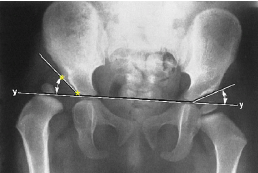

Q what is the name of this measurement? and what is the average + range?

Lateral Bending Sign

assesses segmental convergence toward the bending side during lateral flexion/side-bending (SB).

Each transverse line should increasingly converge toward the bending side from the lumbosacral (LS) junction upward. No average or range is specified.